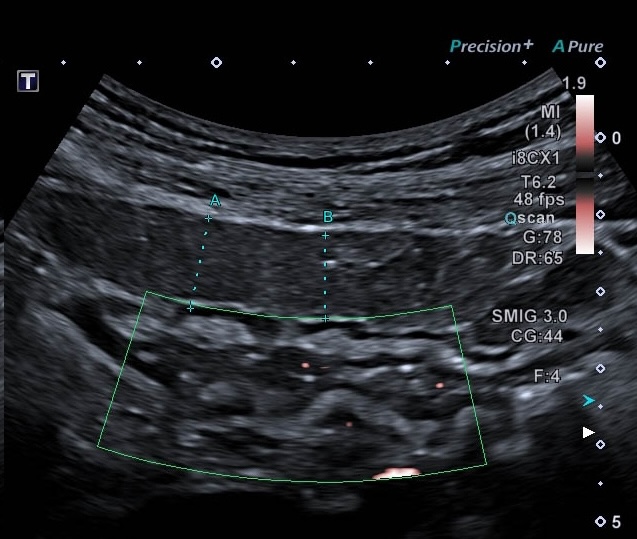

Basse Fréquence inflammation de la graisse autour du colon transverse (maladie de Crohn colique)

- On la mesure mieux sur une coupe transversale.

Coupe transversale permet de mieux aprécier l'inflammation de la graisse